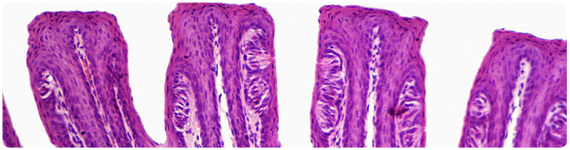

Aunque la base de la percepción del gusto salado ha sido estudiada por años, su mecanismo molecular permanece poco claro. En los roedores, los canales de sodio epiteliales (ENaCs, por sus siglas en inglés) localizados dentro de las membranas de las células gustativas en las papilas fungiformes pueden jugar un importante papel en la percepción de NaCl.